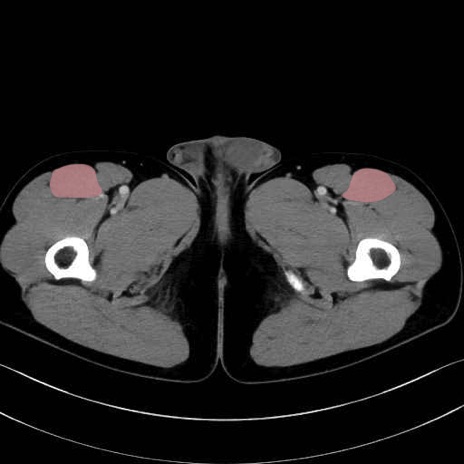

縫工筋 (Sartorius)

大腿直筋 (Rectus femoris)

外側広筋 (Vastus lateralis)